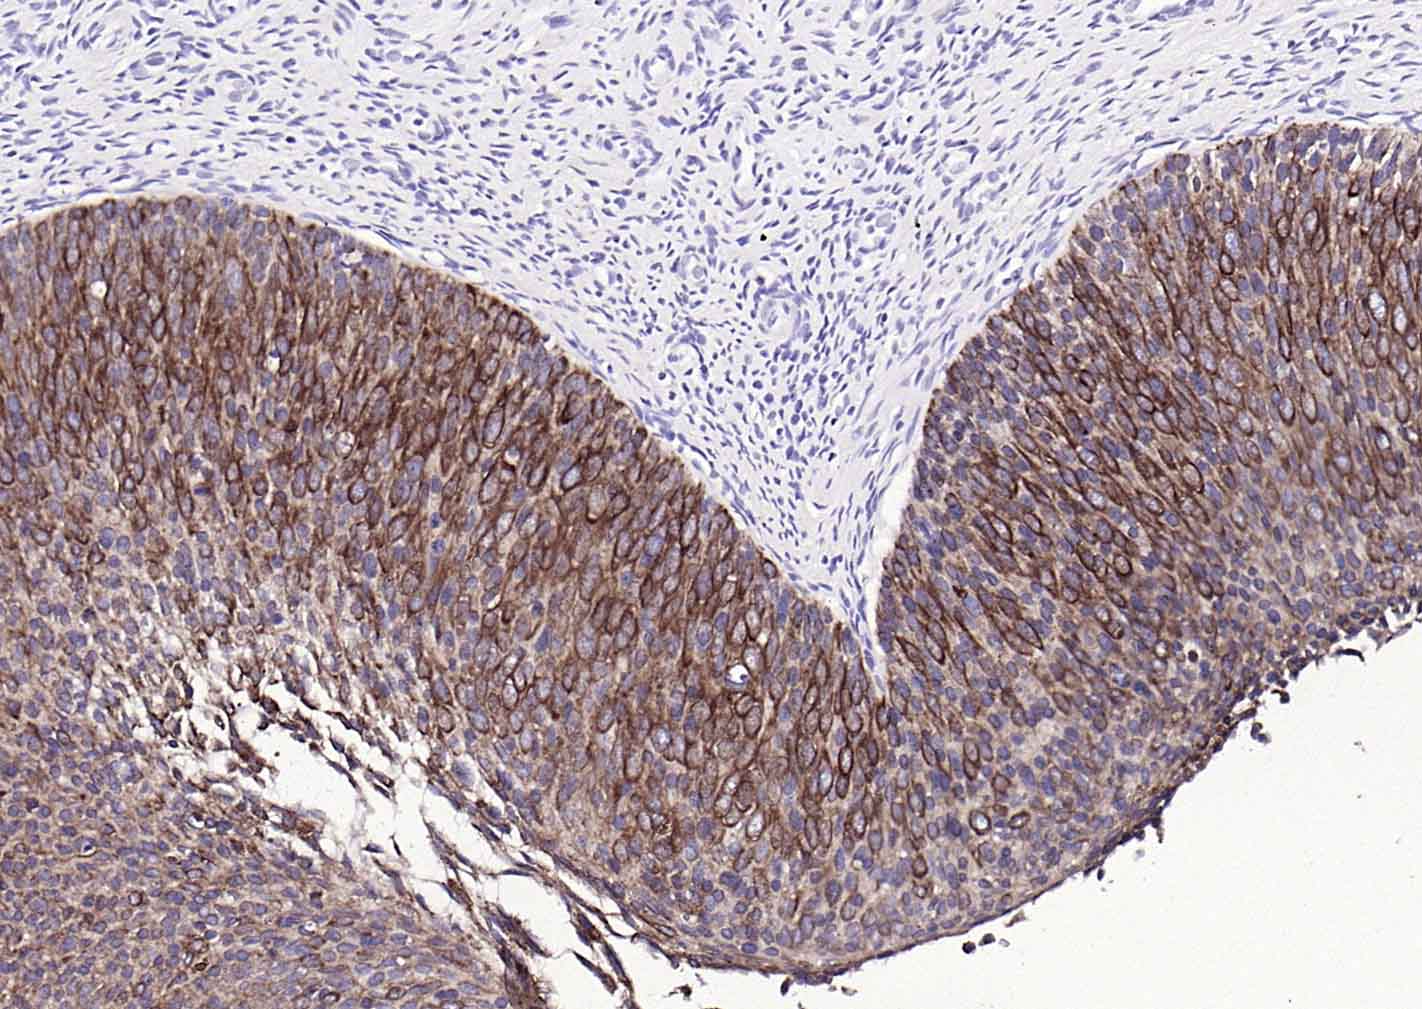

P-CK广谱细胞角蛋白(AE1/AE3)主要标记角化上皮、复层鳞状上皮、复层上皮、增生的角化上皮和单层上皮,用于鳞癌,各种腺癌 、移行上皮癌,小细胞癌,恶性间皮瘤、生殖细胞肿瘤,部分滑膜肉瘤、平滑肌肉瘤等表达。

IHC-PHuman, Mouse, Rat1:100-500